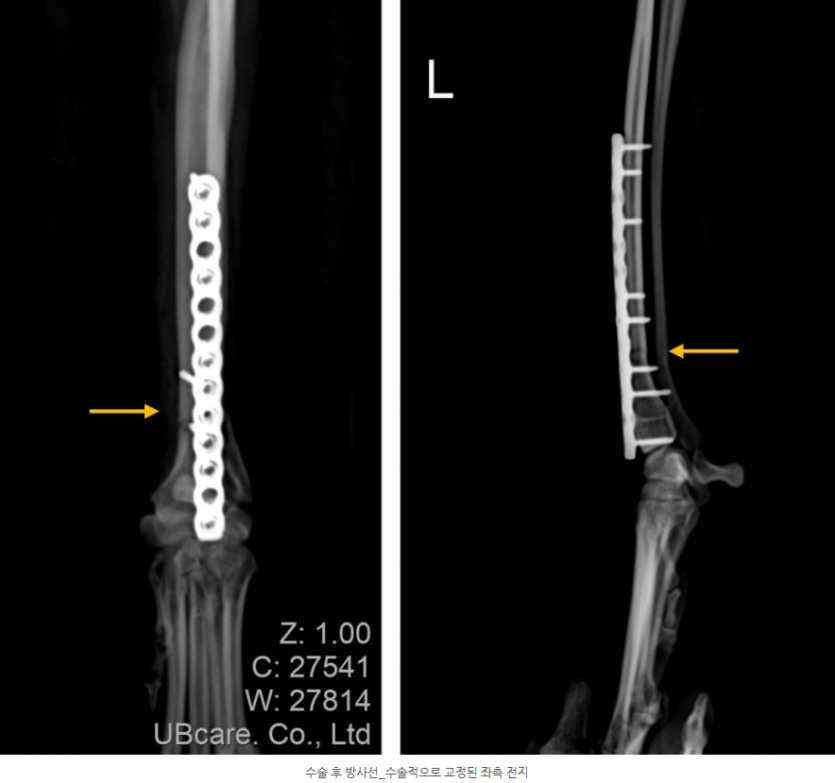

우측에 이어 좌측 요골과 척골의 골절도 확인이 되었는데요, 특히 이탈리안 그레이 하운드의 경우 뼈가 가늘고 길기 때문에 이 처럼 외상에 의한 골절에 취약할 수 밖에 없습니다.

좌측 전지 골절 수술_골절된 골편의 정렬을 맞춘 모습

동일한 방법으로 수술이 진행되었고, 레이저 물리치료를 병행하여 치료 하였습니다. 골절 수술을 한 경우, 수술 후에도 주기적으로 뼈의 유합, 고정 장치의 위치, 뼈의 배열 등을 체크해야합니다. 특히, 뼈가 얇고 작은 아이들의 경우 수술 후 뼈가 붙은 후에도 골절 수술 부위에 부작용이 발생할 수 있기 때문에 주기적인 체크가 필수적입니다.

수술 후 방사선에서도 플레이트와 스크류가 잘 유지되며 골절된 뼈가 잘 붙어가는 것이 확인되었습니다.